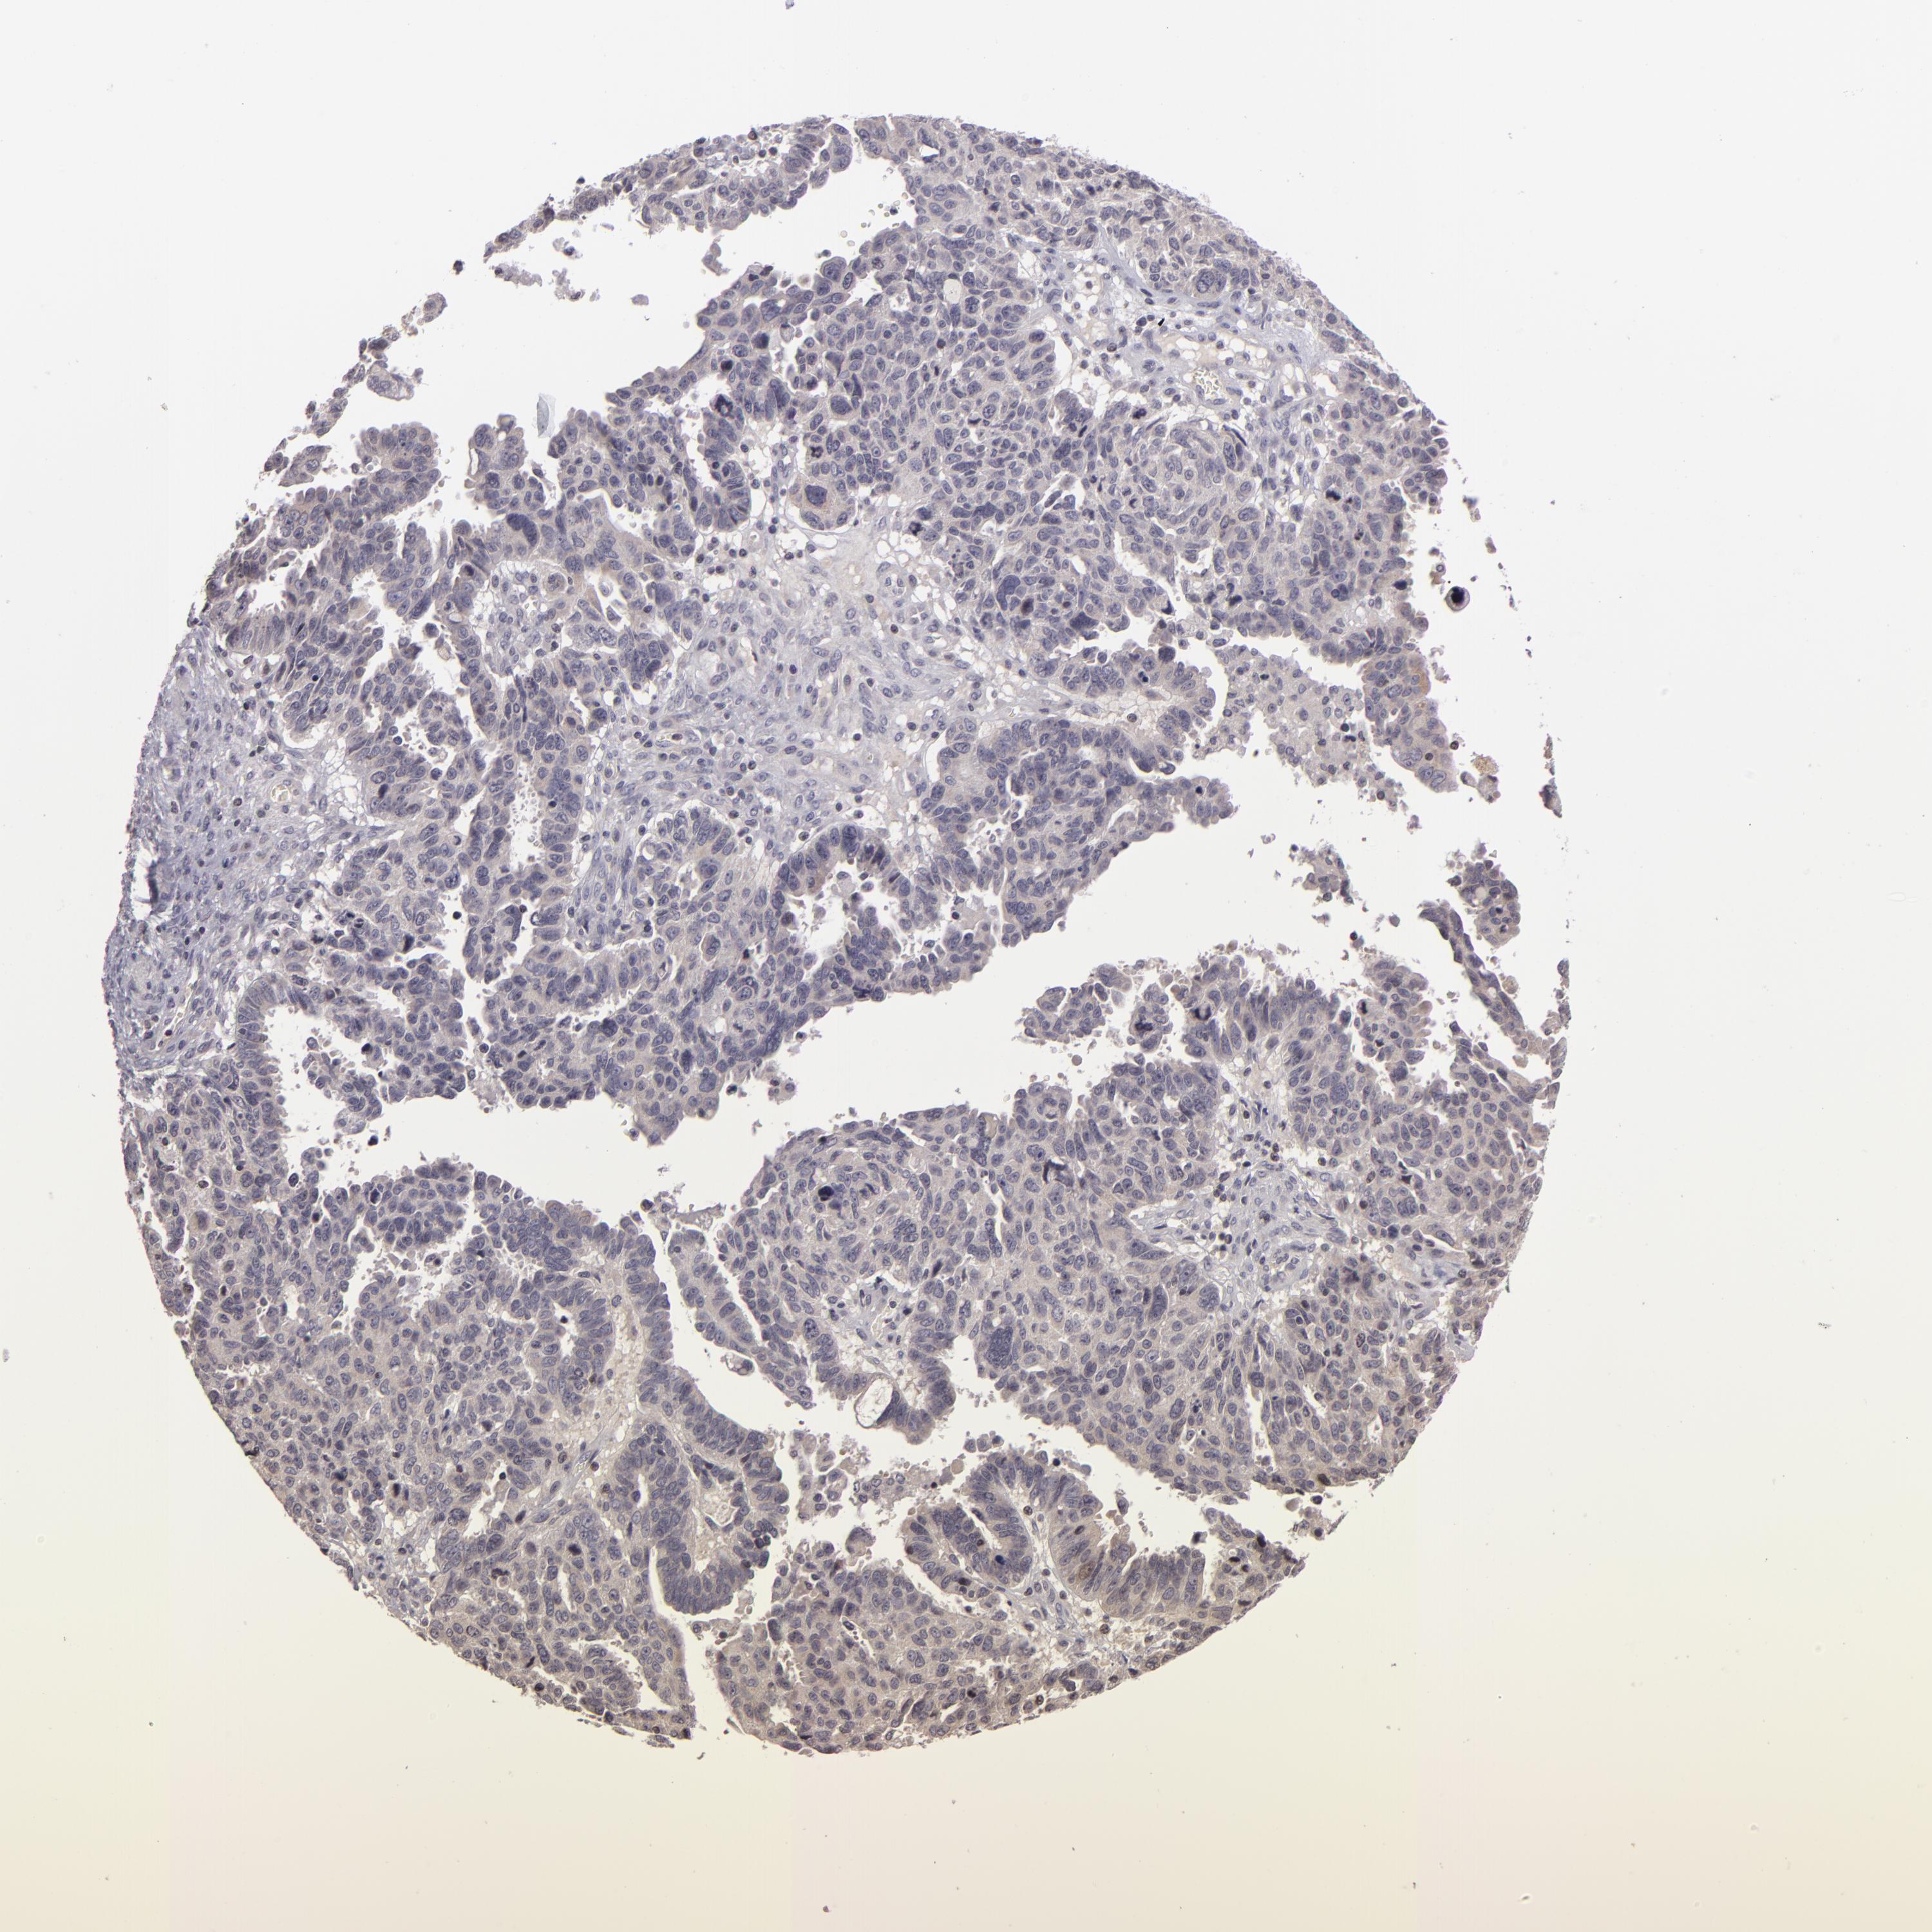

OVARIAN CANCER - Protein expressioni

A mouse-over function shows sample information and annotation data. Click on an image to view it in a full screen mode. Samples can be filtered based on level of antibody staining by selecting one or several of the following categories: high, medium, low and not detected. The assay and annotation is described here.

Note that samples used for immunohistochemistry by the Human Protein Atlas do not correspond to samples in the TCGA dataset.

Antibody stainingi

Antibody staining in the annotated cell types in the current human tissue is reported as not detected, low, medium, or high, based on conventional immunohistochemistry profiling in selected tissues. This score is based on the combination of the staining intensity and fraction of stained cells.

Each image is clickable and will lead to virtual microscopy that enables deeper exploration of all samples and also displays staining intensity scores, fraction scores and subcellular localization as well as patient and tissue information for each sample.

Antibody HPA048741

Antibody CAB001983

Cystadenocarcinoma, serous, NOS

Carcinoma, NOS

Cystadenocarcinoma, mucinous, NOS

Carcinoma, endometroid